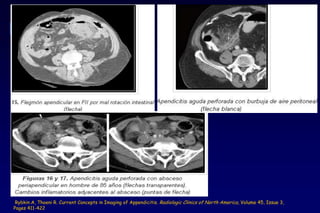

• Perforaciones (25.8%) y peritonitis

- Infrecuente en las primeras 12 hrs de evolución

- Hallazgo qx 50% presente en >50 años y en <10 años

• Abscesos intraabdominales y pélvicos

• Plastrón apendicular

Rybkin A, Thoeni R. Current Concepts in Imaging of Appendicitis. Radiologic Clinics of North America, Volume 45, Issue 3,

Pages 411-422